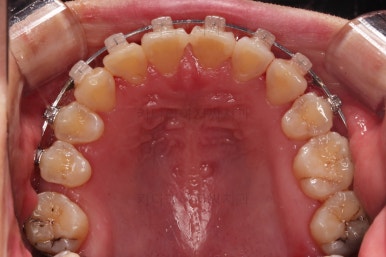

1. 초진

초진 시 입안의 모습입니다.

당장 눈에 띄는 부분은 아래 앞니 사이에 틈새가 있어 치석도 많이 쌓여있는 상황이고요.

윗니-아랫니를 각각 보면 치아가 썩고 부러져 뿌리만 남은 치아가 많이 보입니다.

남은 치아들도 곳곳에 충치가 보이고요.

또 전반적으로 앞니가 앞으로 밀려나와 뻐드러져 있는 모습도 관찰되네요.

브라켓을 부착합니다.

이번 환자분이 선택하신 장치는 데이몬 클리어라고 하는 자가결찰 세라믹 장치인데요.

일반적으로 흔히 아시는 클리피씨 장치에 비해서 철사를 잡아주는 뚜껑까지 세라믹으로 되어 있어서 아마도 현존하는 세라믹 장치 중에서는 가장 심미적인 장치라고 볼 수 있습니다.

치열을 정리해 나갑니다.

치열이 매우 가지런해졌고, 아래 앞니 사이 틈새도 점점 오므려져 가고 있습니다.